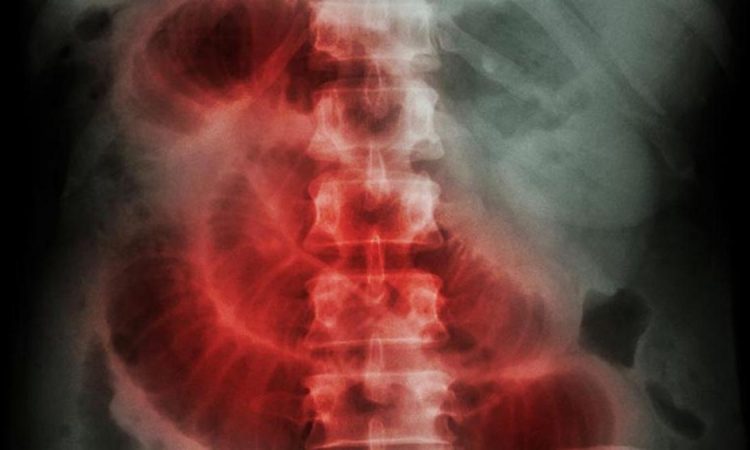

Santo Domingo. – Cleveland Clinic atendió a Luis Isaías Franco Hidalgo, un paciente dominicano diagnosticado con una fístula intestinal y sepsis, quien relató su enfermedad la cual presentó una complicación que genera dolor abdominal severo, reducción del apetito, vómitos, inflamación del vientre, gases fuertes y estreñimiento, además de una obstrucción intestinal.